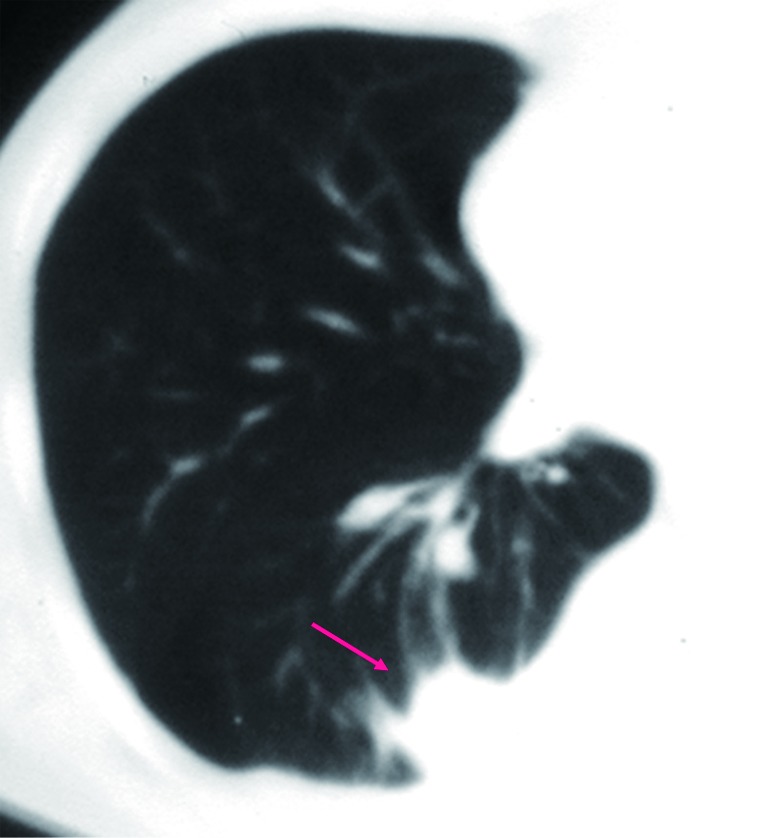

Figure 12.

PET-CT shows a case of atypical adenomatous hyperplasia with a SUVmax of 1.42.

In most studies, the sensitivity of 18F-FDG PET-CT tends to be higher than its specificity for assessment of SPN. Many benign conditions, such as granulomatous (for example histoplasmosis or tuberculosis) and inflammatory processes, can mimic malignant nodules and produce false-positive results (Figure 13) (86). On the other hand, false negative results for SPN characterization on PET-CT can occur in three main settings: small lesion size, low tumor metabolic activity, and hyperglycemia. Small lesions (<1 cm) are challenging due to limited spatial resolution of PET, which is approximately 7 mm for modern scanners (7). Some highly differentiated malignant tumors have relatively little metabolic activity and low rate of proliferation, resulting in false-negative PET-CT. FDG PET is falsely negative in around 50% of patients with bronchioloalveolar carcinoma (87), or adenocarcinoma in situ (88-90). In addition, metastasis from certain primary malignancy, such as renal cell carcinoma, testicular or prostate cancer, may show little FDG tracer accumulation and may even be undetectable on PET-CT (91). False negative FDG PET-CT scans may also occur in patients with hyperglycemia (77). Some authors have proposed dual time point FDG-PET imaging, using the change in SUVmax between early and delayed scans to help differentiate benign and malignant SPNs (92). However, the role of dual time point PET imaging (DTPI) has been disputed by some authors (93). A meta-analysis on diagnostic performance of dual time point FDG-PET imaging in assessing lung nodules reported similar sensitivity and specificity to single time point FDG-PET (94). Further studies are needed to clarify this point.